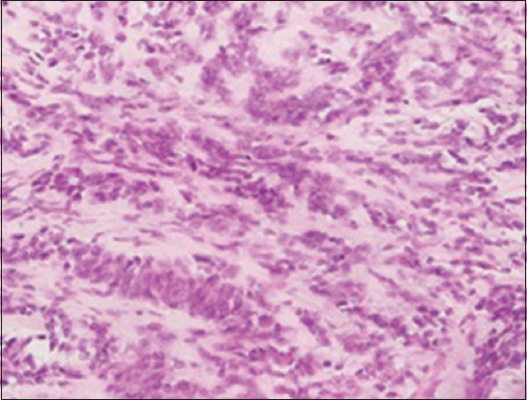

Case description: We present two pediatric cases of renal Ewing sarcoma. Both cases emphasize the significance of accurate diagnosis, multimodal treatment, and long-term follow-up in achieving favorable outcomes. Accurate diagnosis of renal Ewing sarcoma is crucial for effective management. Multimodal treatment involving neoadjuvant chemotherapy, surgical resection and staging with lymph node sampling, and chemotherapy continuation has shown promising results in our cases. Long-term follow-up is essential for monitoring disease progression and ensuring optimal outcomes.